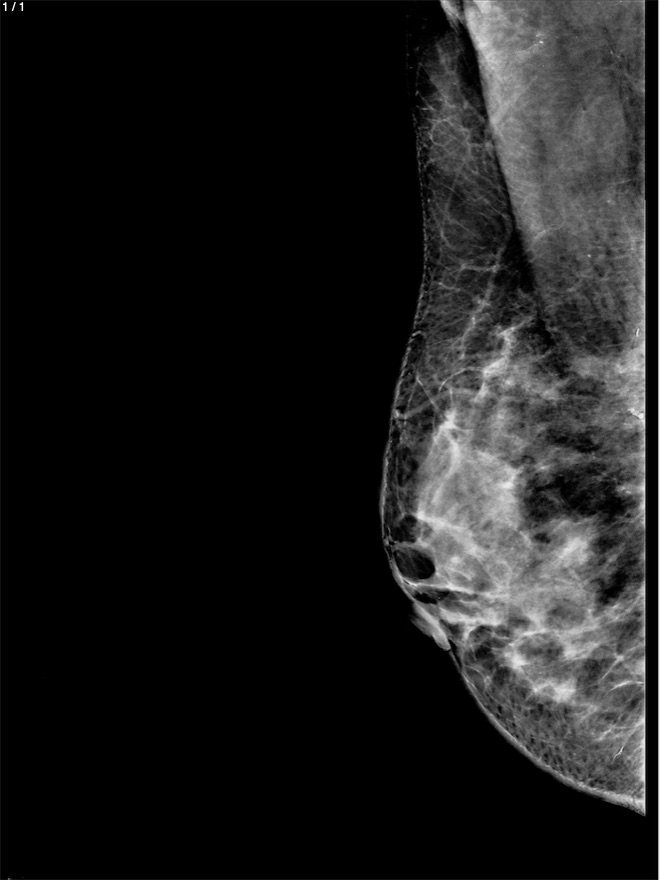

Adelina Martha Perez Roblero - Unnamed